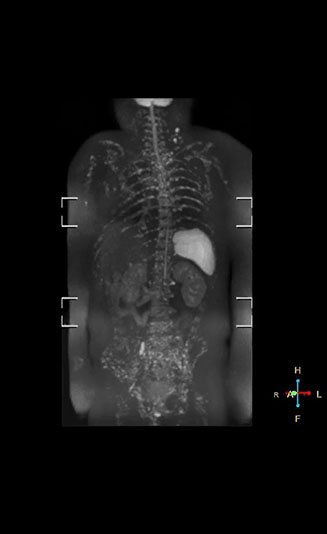

“Once Ingenia was available, our first goal was to shorten the exam time of our scan,” says Mr. Naka. The next goal was to create a protocol that provided more clinical information.

“When we limited the scan coverage to the area from neck to femur, we could fit more clinical information in approximately the same scan time. So, we added coronal mDIXON, sagittal T1-weighted, and sagittal STIR sequences to our examination, instead of performing only axial DWIBS and coronal single-shot TSE scans.”

The single shot T2-weighted TSE images are used for morphology and compared to DWIBS images to identify T2 shine-through. Sagittal STIR images are used in patients with inflammation or bone metastasis.

“With coronal DWIBS, we can perform a full whole body exam, including other sequences, within 30 min.”

“When we use a coronal DWIBS acquisition, we can perform a full whole body examination, including other required sequences, within 30 minutes,” he says.